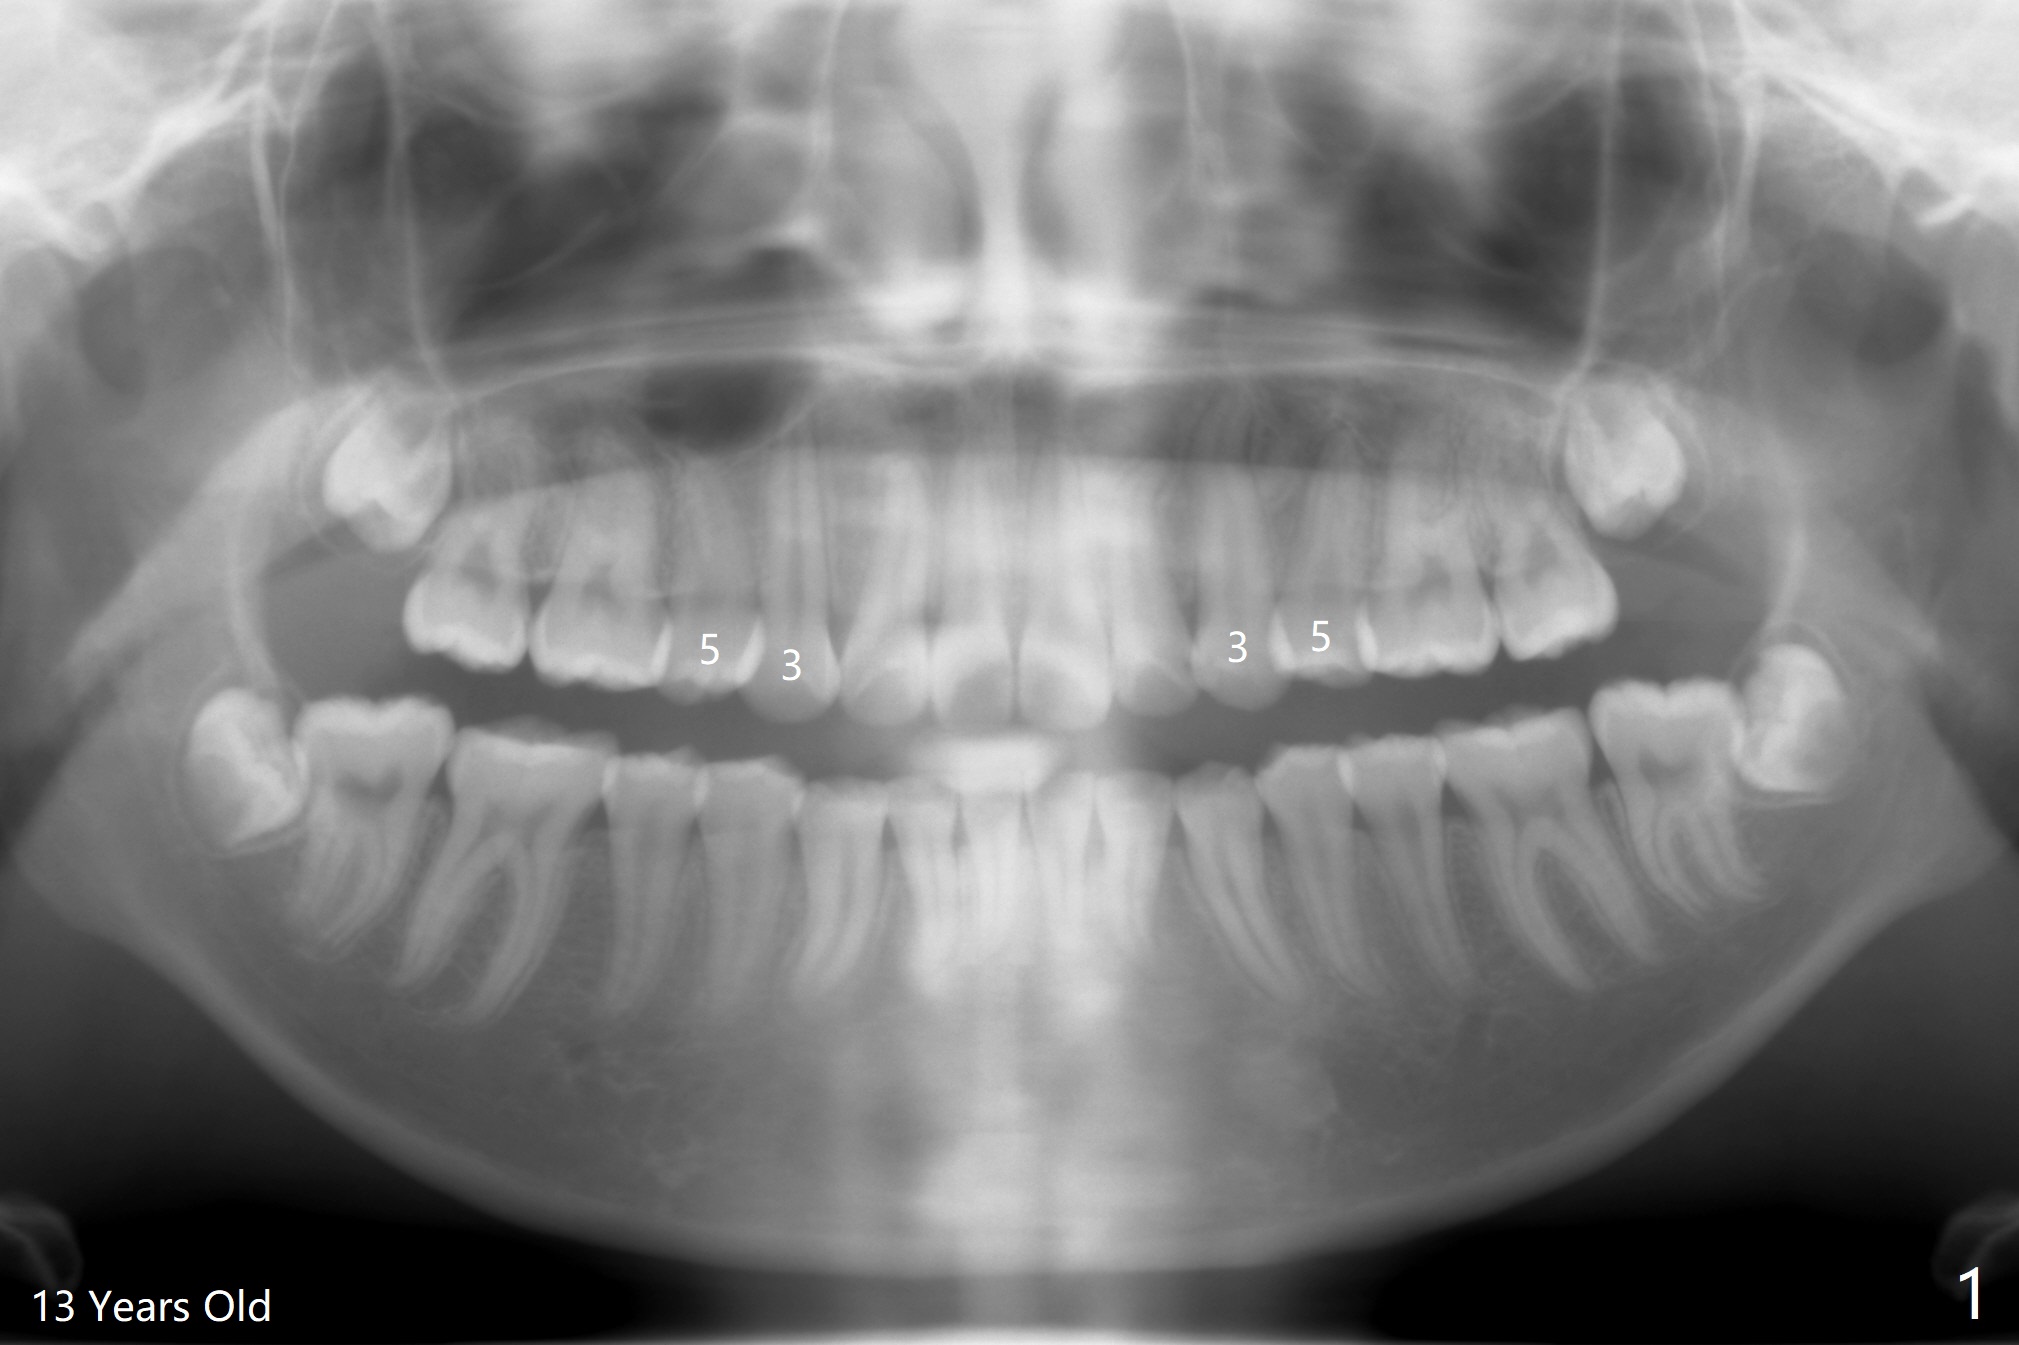

18岁女要求上大学前拔除智齿(图二),十三岁上四已经为了矫正而拔除(图一),所以现在只需要拔除下八,后者接近水平阻生,冠部可能位于下七远中颊侧(图三,四 *),所以附加切口应在七近中(红线)。智齿拔除后根部有两个牙槽窝(图五,六 *)。在右侧,塞入两个胶原塞(图七:1,2,collagen plug),其中一个末端剪开塞入根部牙槽窝。而左侧,使用一个胶原塞,但事先剪成两半(图八:1,3),第一部分也剪成燕尾,插入根部牙槽窝(1),然后在七远中放置骨水泥(1 cc Bond Apatite,2 红色),在后者上面放入胶原塞另外一半(3)。最后两侧都使用4-0 PGA 缝线。